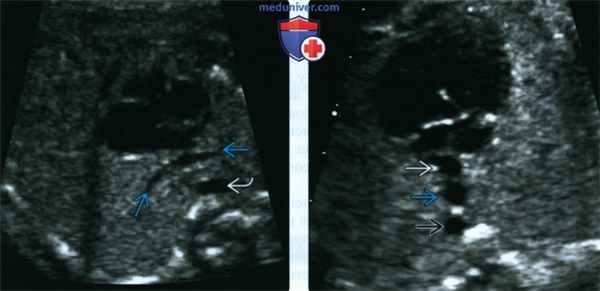

(Слева) УЗИ в поперечной плоскости, слегка наклоненной из плоскости четырехкамерного среза. Определяется признак «ветки» - аномальное слияние легочных вен, расположенное между сердцем и нисходящей аортой.

(Справа) УЗИ в поперечной плоскости. Правопредсердный изомеризм, ТАДЛВ. Аорта находится на той же стороне, что и нижняя полая вена. Позади предсердия определяется третий сосуд, образованный в результате слияния всех четырех легочных вен.